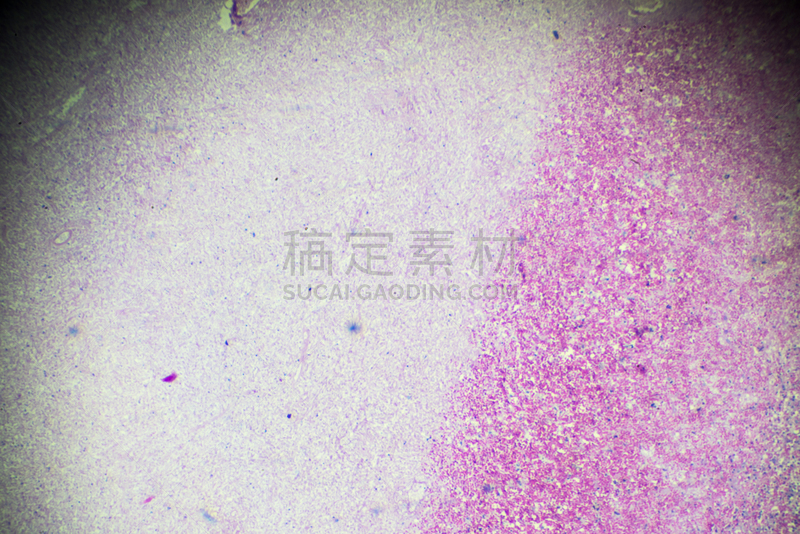

详情